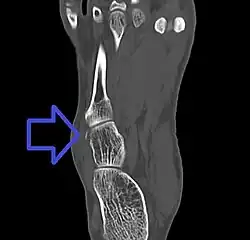

Cuboid fracture

A cuboid fracture is a fracture of the cuboid bone of the foot. Diagnosis is by X-ray imaging, magnetic resonance imaging, or bone scan.[1] Treatment may be conservative or involve surgery, depending on the type of fracture.[1] They are rare.[1]